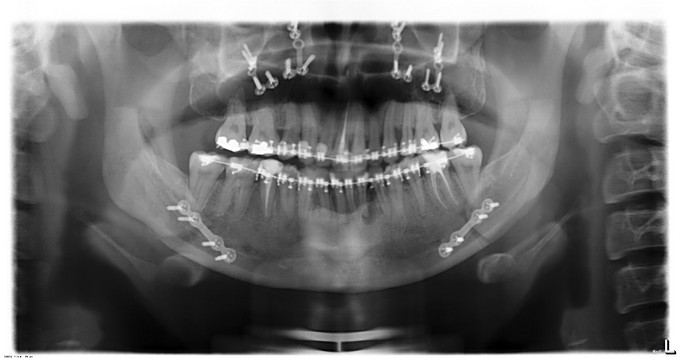

发现下颌前突、上颌后缩数年,于13年行正畸治疗。今为进一步治疗来我院就诊,门诊以"下颌前突、上颌后缩"收入院。

面部发育一般,中线左右对称,上中下比例不协调,上颌后缩,下颌前突,颏顶点正中。左侧颞下颌关节无弹响无疼痛动度正常,右侧颞下颌关节无弹响无疼痛动度正常。张口度4.0cm,开口型正常。上下牙弓关系协调,前牙反合约0.6cm,龋齿无,牙周病无。

入院诊断:1.下颌前突2.上颌后缩3.偏颌畸形,出院诊断: 1.下颌前突2.上颌后缩3.偏颌畸形4.双侧上颌窦粘液囊肿,全麻下行“上颌LefortI型颌骨前徙术+骨内坚固内固定术+双侧下颌升支矢状劈开后退术+双侧下颌骨去骨皮质术+骨内坚固内固定术+双侧邻近瓣转移修复术+双侧上颌窦粘液囊肿摘除术”